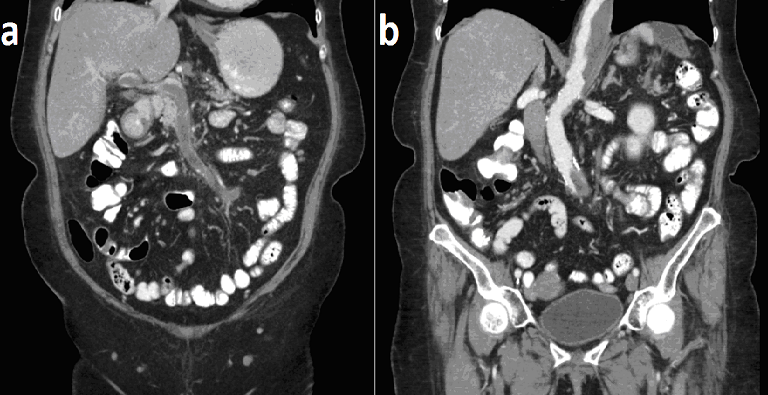

A 61-year old Caucasian woman, presented to the Emergency Department due to a four-week history of vomiting, diarrhea and abdominal pain. Physical examination revealed tenderness in the upper abdomen and normal bowel sounds. A CT was performed and the patient was admitted. A CT scan of the chest and the abdomen revealed a chronically dissected Stanford B thoracoabdominal aneurysm with mural thrombus, thrombosis of the celiac, hepatic, splenic and superior mesenteric arteries with collateral circulation, thrombosis of the portal and superior mesenteric veins and a splenic infarct. Dissection of an aneurysm is a catastrophic complication with high mortality and morbidity, thus an invasive treatment is often warranted with either surgery or endovascular repair. On the other hand, portal thrombosis is associated with inherited or acquired procoagulant states (like Factor V Leiden), hematologic diseases (like myeloproliferative diseases), cirrhosis, abdominal surgery or trauma and intra-abdominal inflammatory conditions. Its treatment involves anticoagulation or rarely, thrombolysis or thrombectomy. Both chronic dissection of the abdominal aneurysm and the portal vein thrombosis can cause abdominal pain, nausea, and other gastrointestinal symptoms secondary to bowel hypoperfusion. Diagnosis: chronically dissected Stanford B thoracoabdominal aneurysm and thrombosis of the celiac, hepatic, splenic and superior mesenteric arteries with collateral circulation, thrombosis of the portal and superior mesenteric veins and a splenic infarct.